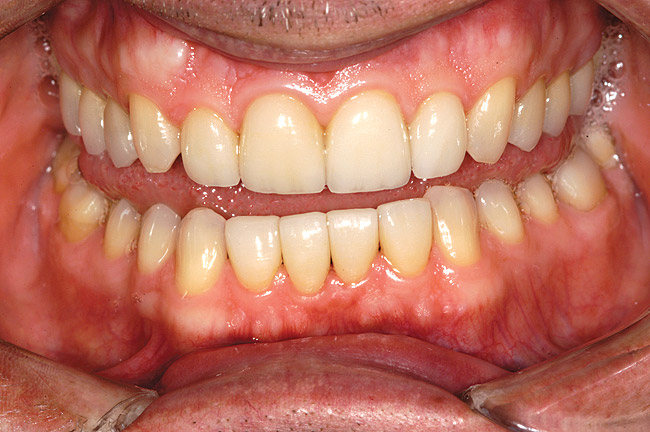

Figure 1a  A patient presents with large direct composite restorations and multiple crack lines in teeth Nos. 18 and 19. Tooth No. 19 was symptomatic to biting pressure.

Figure 1a

While in vitro studies do not definitively demonstrate a correlation between fracture resistance and cuspal coverage, cuspal coverage is still considered important in instances where the remaining tooth structure is less than one third to one half of the intercuspal distance.22,23 Other factors that support cuspal coverage of posterior teeth are the position of the tooth within the arch, with molars subject to greater bite forces and, therefore, exhibiting a greater need for cuspal coverage.24,25 Cracked teeth also warrant cuspal coverage (Figure 1A through Figure 1C).26,27